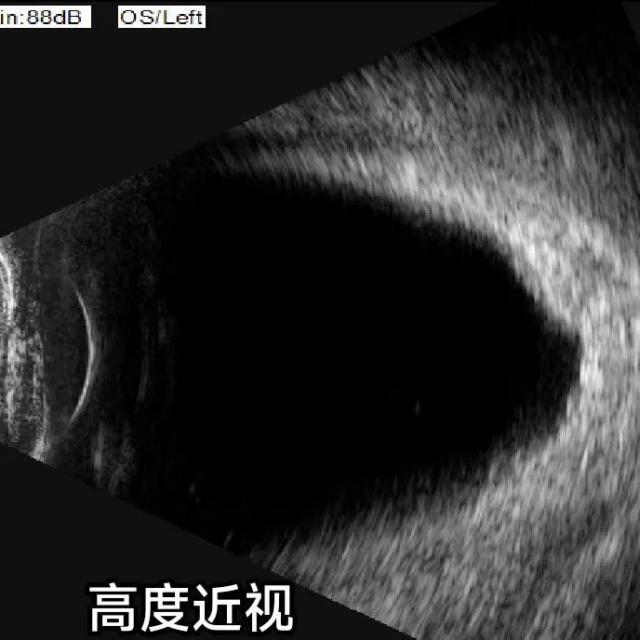

眼部B超檢查

儀器:B型超聲診斷儀

功能:排查眼內、眶內病變,如視網膜脫離、眼內及眼眶腫瘤等。

結果示例